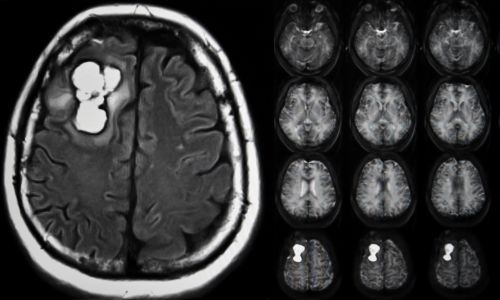

Tumores cerebrales

Manejo integral con técnicas microquirúrgicas y de mínima invasión.

- Meningioma

- Adenoma de hipófisis

- Tumores del sistema nervioso central (p. ej., gliomas/ependimomas)